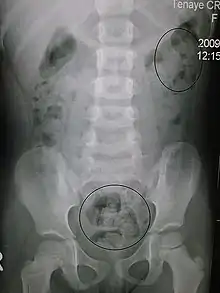

In order to correctly manage neurogenic bowel dysfunction it is important to accurately diagnose it. This can be done by a variety of methods, the most commonly used would be taking a clinical history and carrying out physical examinations which may include: abdominal, neurological and rectal examinations. [16] Patients may use the Bristol Stool Chart to help them describe and characterise the morphological features of their stool, this is useful as it gives an indication of the transit time.[17] An objective method used to evaluate the motility of the colon and help with diagnosis is the colon transit time.[18] Another helpful test to diagnose this condition may be an abdominal X- ray as this can show the distribution of the faeces and show any abnormalities with the colon for example a megacolon.[13] Methods used for diagnosis may vary depending on if the patient is incontinent or constipated